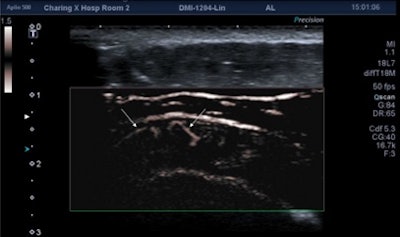

While flow was demonstrated on both power Doppler and SMI in 58 cases, SMI alone showed vascularity in 40 cases. No cases of vascularity were shown on power Doppler but not on SMI. In 18 cases, no flow was detected by either technique. This difference in performance between power Doppler and SMI was statistically significant (Fisher's exact test: p < 0.001).

Acute case of supraspinatus tendinitis. SMI shows abnormal microvasculature (arrows) within the inflamed tendon. Image courtesy of Dr. Adrian Lim.In more than half the cases where flow was identified using both techniques, SMI was judged to be either moderately or markedly better than power Doppler. This difference was also statistically significant (p = 0.02).